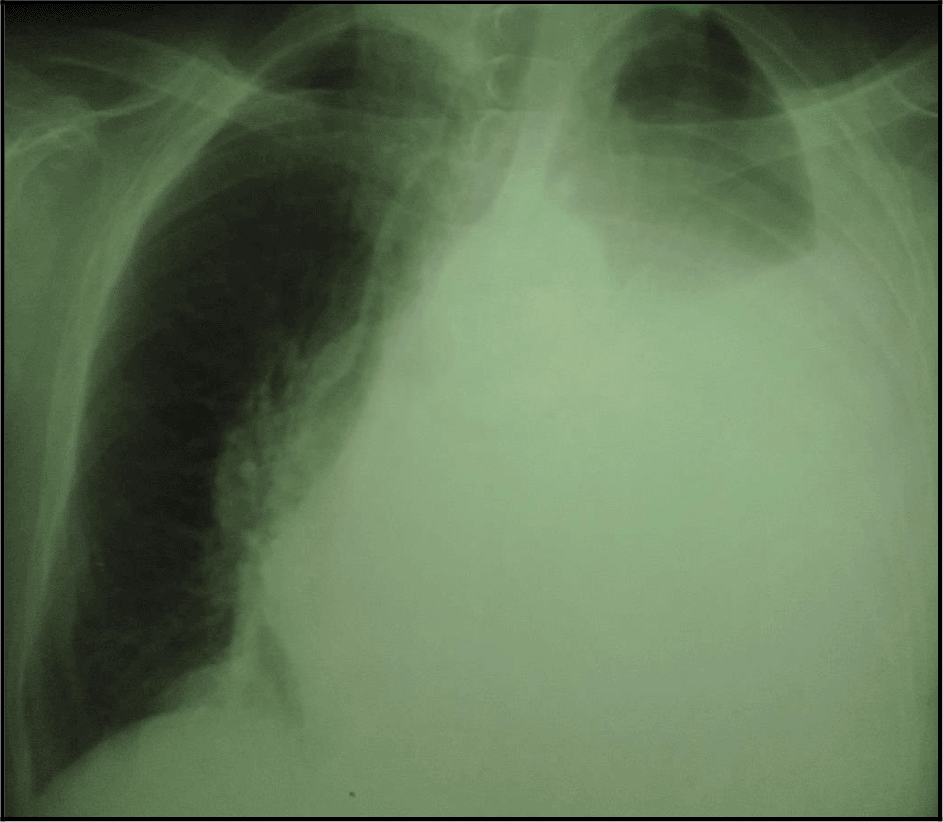

The chest X-ray showed a left-sided pleural opacity with signs of compression (Figure 1). So, an exploratory and evacuating ultrasound-guided pleural puncture was immediately performed. The thoracic ultrasound revealed a massive anechoic, free left pleural effusion associated with many pleural nodules (Figure 2). Therefore, a malignant origin was suspected. Analysis of the pleural fluid showed a serohaematic exudative fluid, with a predominantly lymphocyte formula (80%). A Gram stain fast bacilli (AFB) stain and cultures for (bacterial and tuberculosis) were all negative. Besides, we did not find any malignant cell in the pleural puncture cytology.